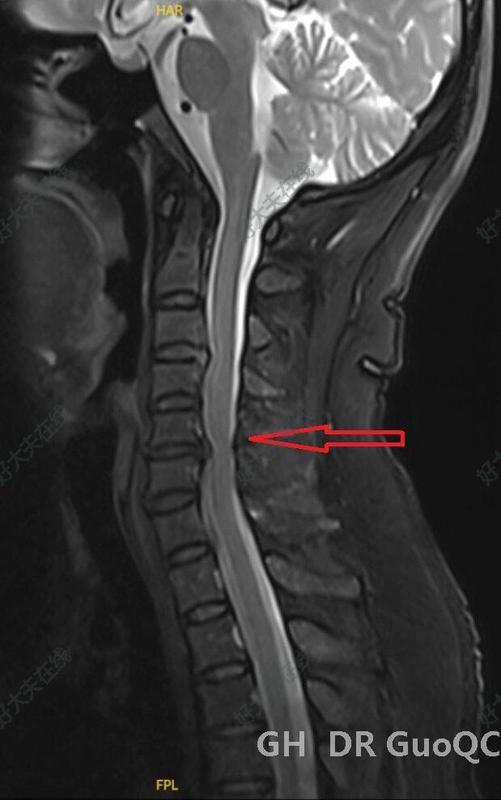

病例79脊髓型頸椎病

郭乾臣醫(yī)生的科普號2023年01月12日332

這樣的病例初次收入應當做前路手術

雖多節(jié)段壓迫,但主要是根性癥狀,神經根孔狹窄。這種前后壓迫程度即使有髓性癥狀也可以通過前路ACDF手術解決,這種病例不是頸椎后路椎管擴大成形手術的最佳適應癥。而后路椎管擴大成形手術通過間接加壓方式固然對脊髓壓迫解除充分,但無法做到神經根孔的充分減壓,也不能穩(wěn)定脊柱不刺激神經根。